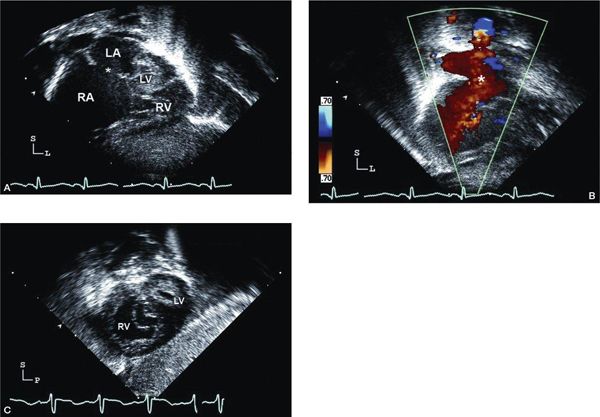

The subcostal four-chamber view typically demonstrates a dilated RA and RV. When angling the transducer posteriorly and imaging toward the base of the LA, the LV either appears very small or is not visualized (Fig. 12.9A [Video 12.7]). It should be immediately apparent when the LV is diminutive or “slit-like” that a significant discrepancy in the size of the RV compared with the LV is present. Once this view is obtained, the echocardiographer should evaluate the mitral valve and the great arteries very carefully. Anterior angulation of the transducer typically shows the dilated RVOT and main PA (MPA), but the very tiny aorta may be difficult to visualize in coronal plane imaging. A large patent ductus arteriosus (PDA) may be seen, essentially representing a continuation of the MPA as the ductal arch, but this is better visualized in subcostal short-axis views. In the setting of cardiovascular collapse, right ventricular function may also be reduced, sometimes significantly so. Tricuspid regurgitation is usually present in this clinical setting.

The atrial septum should be carefully evaluated from the subcostal windows. The size, number, and location of communications from LA to RA should be assessed (Fig. 12.9A–B). Bulging of the atrial septum from the LA into the RA is suggestive of restriction to egress from the LA. Also, in the presence of a restrictive or intact atrial septum, the atrial septum is usually thick and the pulmonary veins are dilated (if normally connected). Color Doppler aids in mapping of the defects with the shunt typically occurring from left to right (see Fig. 12.9B). Alignment of the Doppler cursor parallel with the defect allows estimation of the mean transeptal gradient by tracing the Doppler signal across three cardiac cycles.

Orthogonal plane imaging provides confirmation of the cardiac anatomy. Subcostal short-axis views are excellent for interrogation of the atrial septum. The presence/location of atrial communications should be determined and color Doppler mapping of atrial shunting should be performed. The relative size of the very hypoplastic aorta posteriorly and dilated PA anteriorly is evaluated. Again, by angling the transducer rightward, the continuation of the dilated MPA as the ductal arch is easily demonstrated. Color Doppler interrogation may show bidirectional PDA shunting (typically right-to-left in systole with left-to-right shunting in diastole depending on pulmonary resistance characteristics). The entire aortic arch may be visualized in this view (with definitive imaging obtained from suprasternal imaging). Scanning toward the midventricular level shows the enlarged anterior RV and hypoplastic, posterior LV (Fig. 12.9C). Right ventricular function and tricuspid regurgitation should be assessed.

Figure 12.9. Hypoplastic left heart syndrome (HLHS); subcostal views. A: Long-axis (coronal) image showing very dilated right atrium (RA) and small left atrium. The secundum atrial septal defect (asterisk) is large and unrestrictive. The right ventricle (RV) is hypertrophied, and the left ventricle (LV) and mitral valve are severely hypoplastic (Video 12.7). B: Color Doppler imaging demonstrating nonrestrictive laminar flow across the atrial septal defect (asterisk). C: Short-axis (sagittal) view in the same patient, angled toward the midventricular level showing the anterior, hypertrophied RV. Note the echo-bright LV endocardium often seen in HLHS.